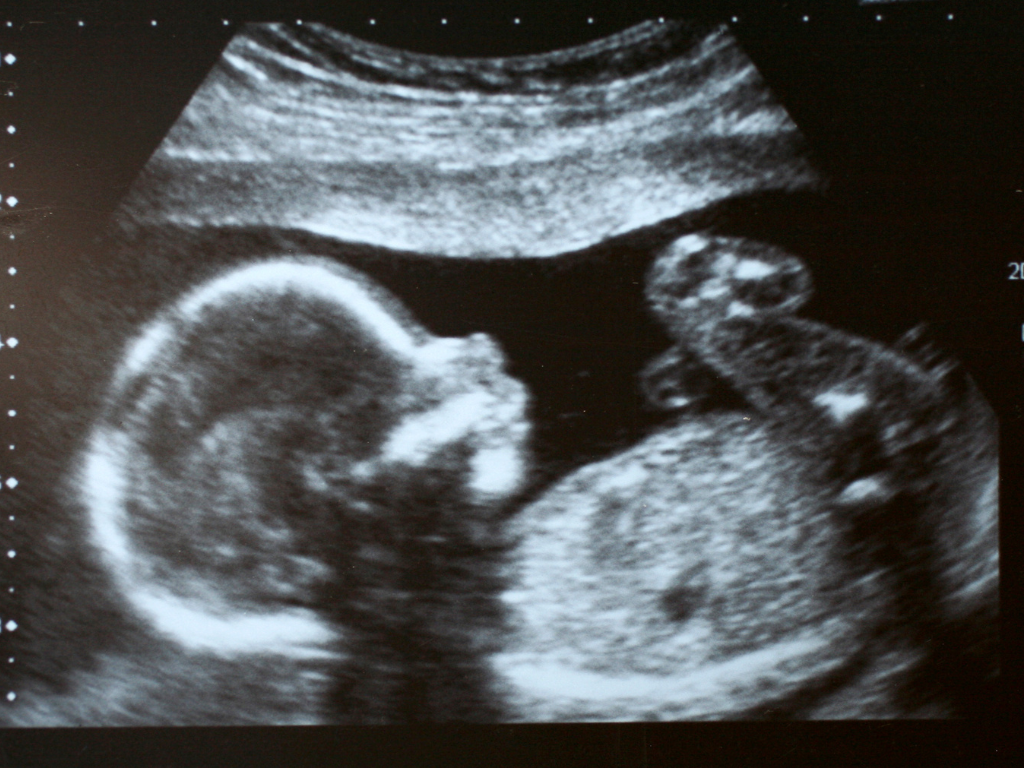

耶穌「道成肉身」,在天使加百列向馬利亞報信的瞬間,就有了生命。同樣地,人類在受孕的那一刻開始就有了生命。子宮是「神的工場」,是孕育生命最神聖的地方,正如先知耶利米和詩人大衛所說,人在母腹中,神已經曉得,並且覆庇生命。人類本應愛惜並保護生命,腹中胎兒是最脆弱、最無辜的一群,卻最被邊緣化、最受剝奪。